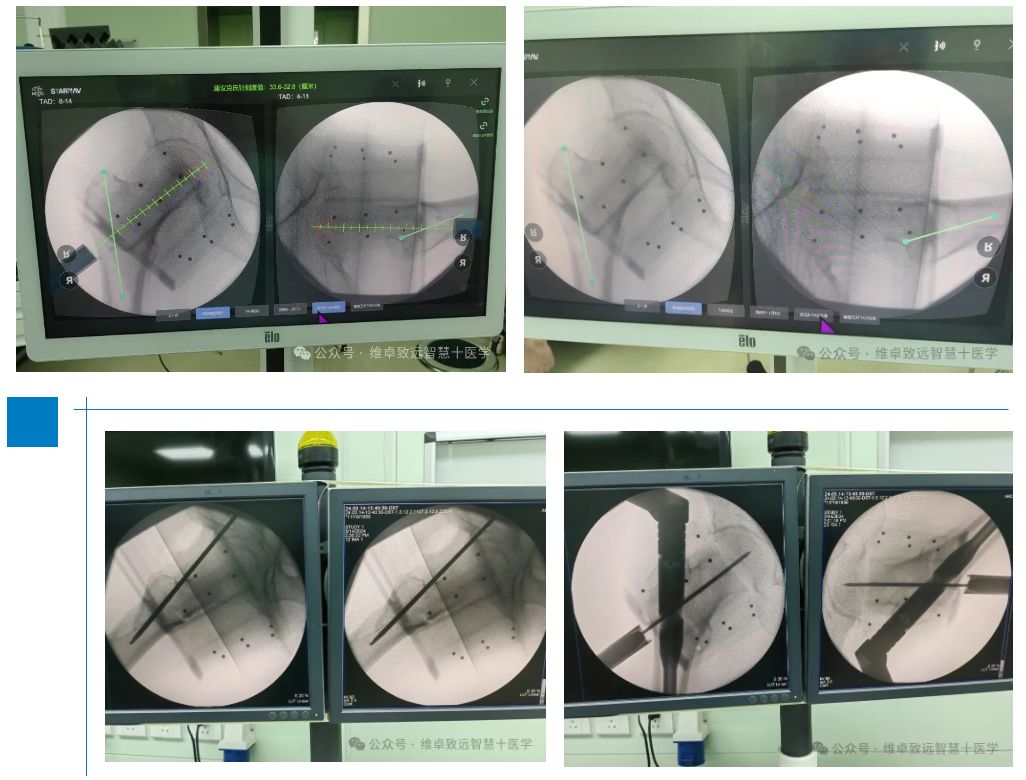

予右腕部手法复位后,建议手术,后转入解放军总医院海南医院治疗。由骨科主任林峰带领团队综合评估后,决定在导航系统的辅助下,进行股骨粗隆间骨折内固定术。 手术中医生在导航的精确引导下,近端切口仅4厘米,术中主钉导针及螺旋刀片导针均一次性置入,体现了手术的微创性、精准性。使用术中C臂机进行透视仅有13次,减少了医生及患者的射线辐射总量。手术过程非常顺利,患者术后良好。这一案例的成功,充分展示了导航手术在骨科领域的优势和应用前景。

术中情况

导航在手术中应用及验证